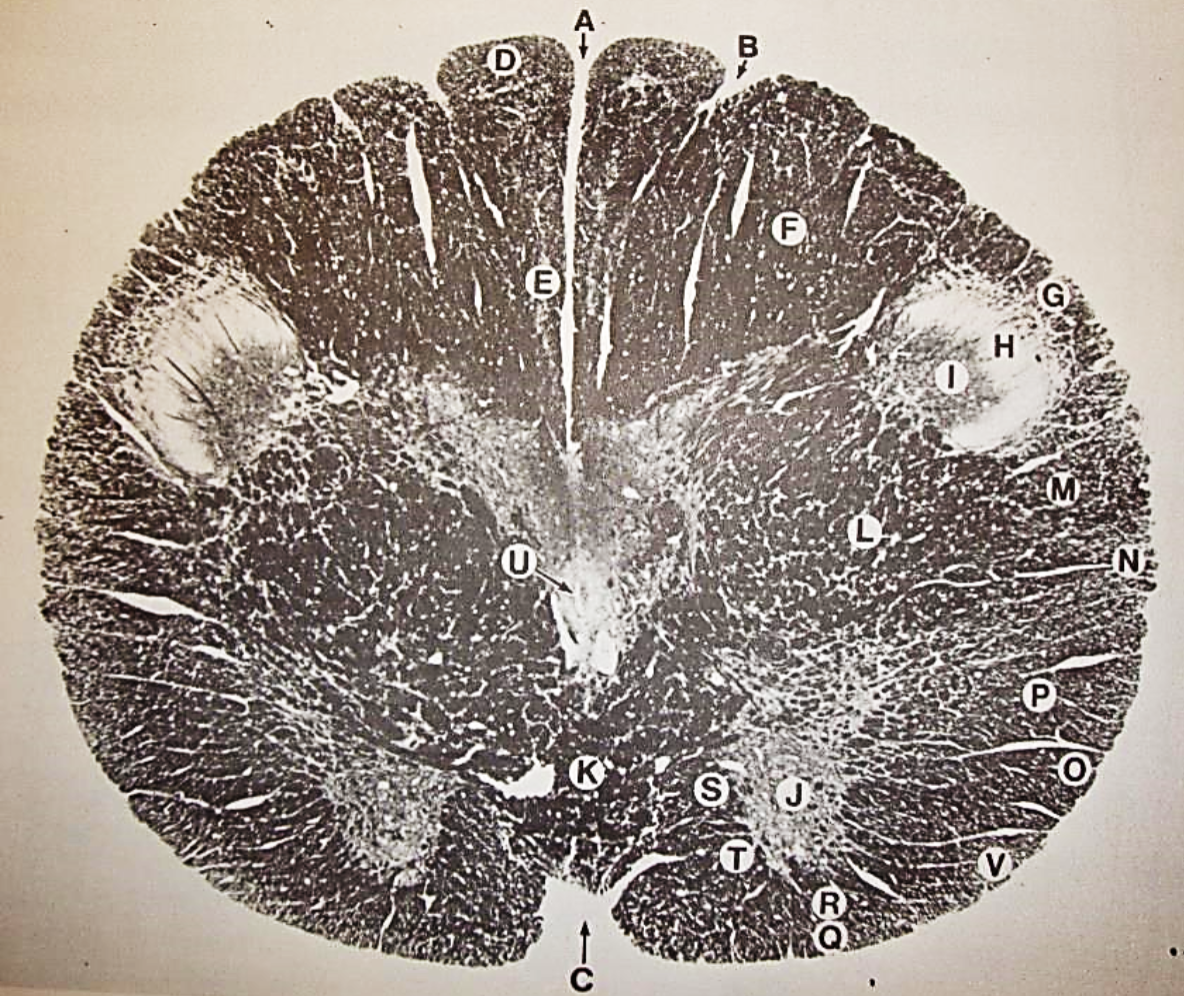

A

Lateral Cuneate nucleus

B

dorsal external arcuate fibers

C + D collectively

vestibular nuclei

C + D collectively

vestibular nuclei

E

dorsal motor nucleus of vagus nerve

F

solitary fasciculus

G

solitary nucleus

H

nucleus ambiguous

I

fascicles of glossopharyngeal nerve

J

hypoglossal nucleus

K

fascicles of hypoglossal nerve

L

dorsal longitudinal fasciculus

M

central tegmental tract

N

inferior olivary nucleus

R

inferior cerebellar peduncle

S

spinal trigeminal tract

T

spinal trigeminal nucleus

U

ventral trigeminothalamic tract

V

pyramidal (corticospinal) tract

W

rubrospinal tract

X

anterior spinocerebellar tract

Y

spinal lemniscus

Z

medial longitudinal fasciculus

a

tectospinal tract

b

medial lemniscus

c

vagus nerve

d

inferior salivatory nucleus